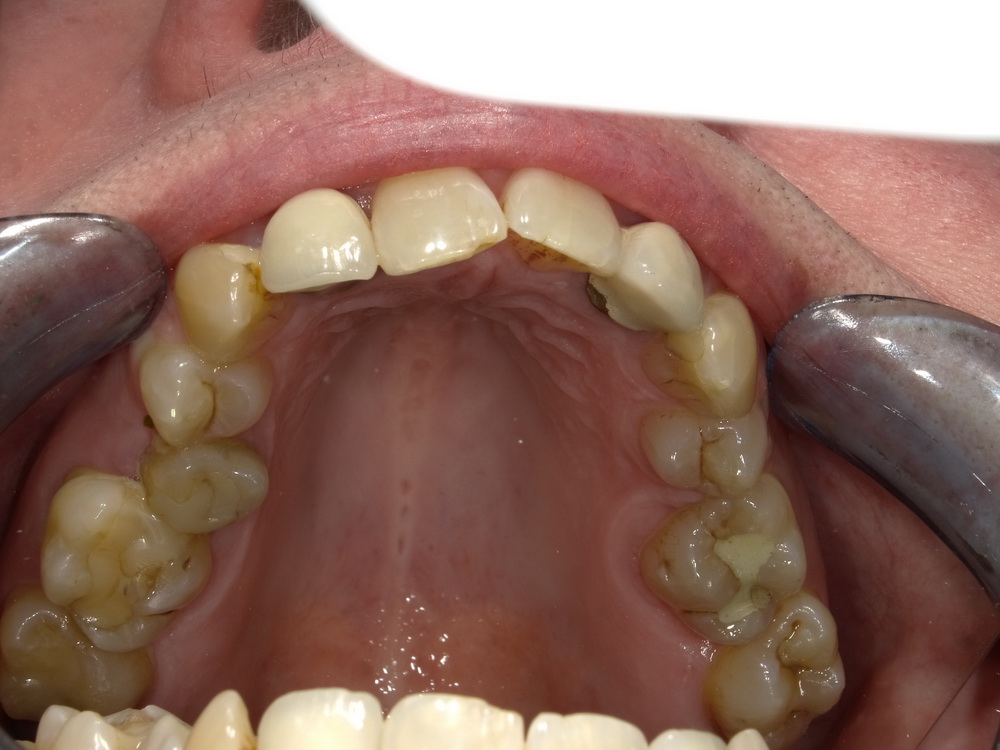

CMD-Patientin ausdem Schaumburger Land beginnt mir der Funktionstherapie

Nun soll es losgehen, was in den vergangenen Monaten systematisch vorbereitet wurde.

Es beginnt mit der Versorgung der Oberkieferseitenzähne mit Laborgefertigten Dauerprovisorien.

Das war der Zustand im September 2025.